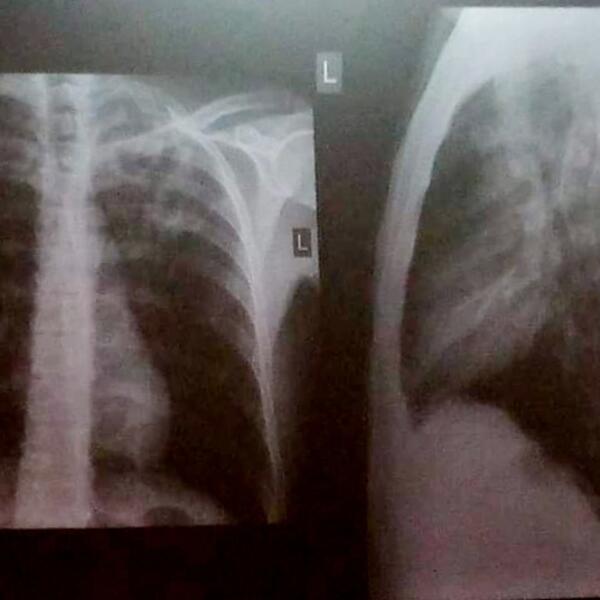

- Najčešći simptomi tuberkuloze su: malaksalost, gubitak apetita i mršavljenje, pojačano noćno znojenje, povišena temperatura, uz kašalj koji je najčešće suv i uporan, a ređe praćen iskašljavanjem sluzi, gnoja ili krvi. Otežano disanje može biti prisutno ako je bolest uznapredovala, a bolovi u grudima se javljaju ukoliko je zahvaćena plućna maramica. Ako su zahvaćeni drugi organi, bolest se manifestuje tegobama vezanim za njih. Preporuka je da se kod svih osoba koje kašlju duže od tri nedelje uradi rendgenski snimak pluća da bi se isključila tuberkuloza ili neka druga plućna bolest, kaže doktorica Plavšić.

Dijagnozu tuberkuloze postavlja isključivo pulmolog na osnovu anamnestičkih podataka, pregleda i obavezne radiografije grudnog koša koja je neophodna i najvažnija dijagnostička metoda.

Snimci pluća pacijenta obolelog od tuberkuloze: